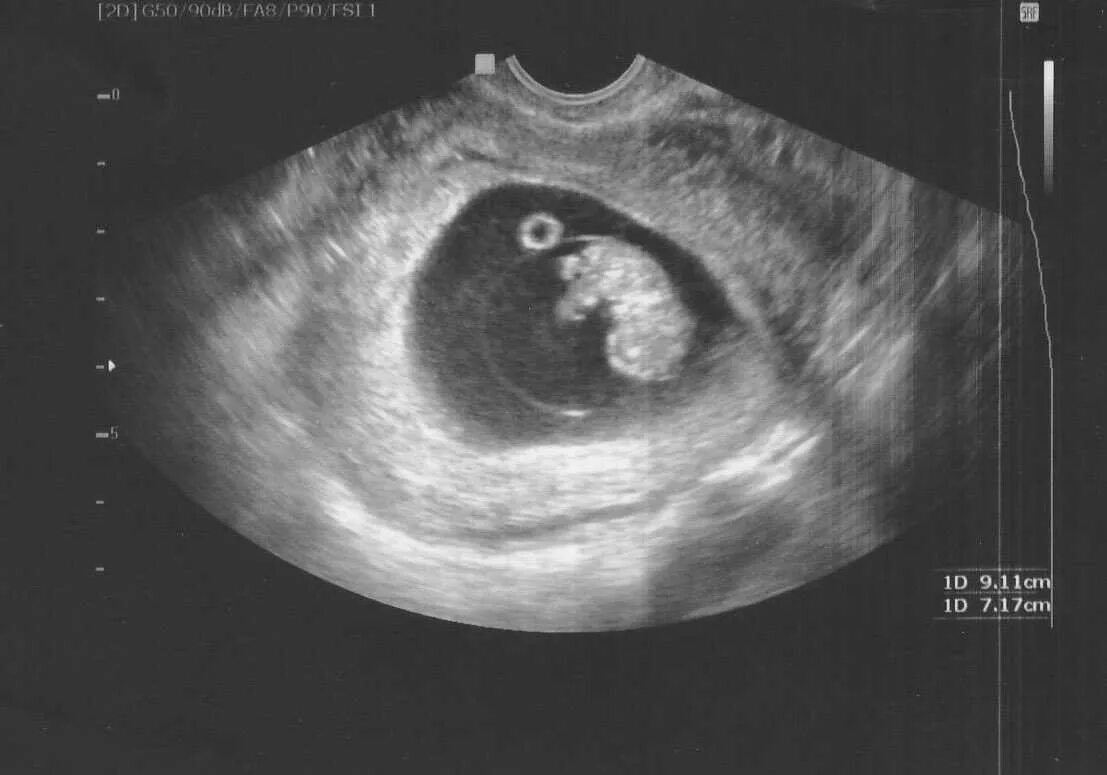

6 недель беременности как выглядит эмбрион